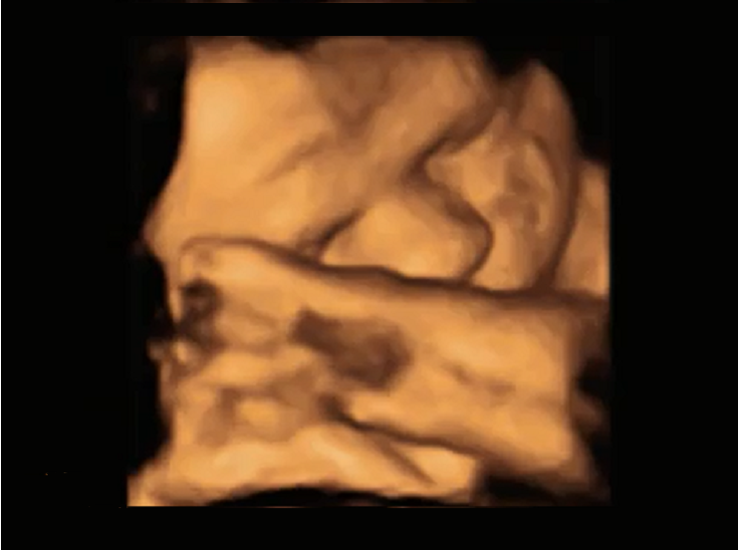

The award of £89,000 will allow Kirsty and her collaborators, Professor Vincent Reid and Professor Gavin Bremner, to use 4D Ultrasound to view unborn babies' behavioural response to newborn cries from around the world as well as different types of speech.